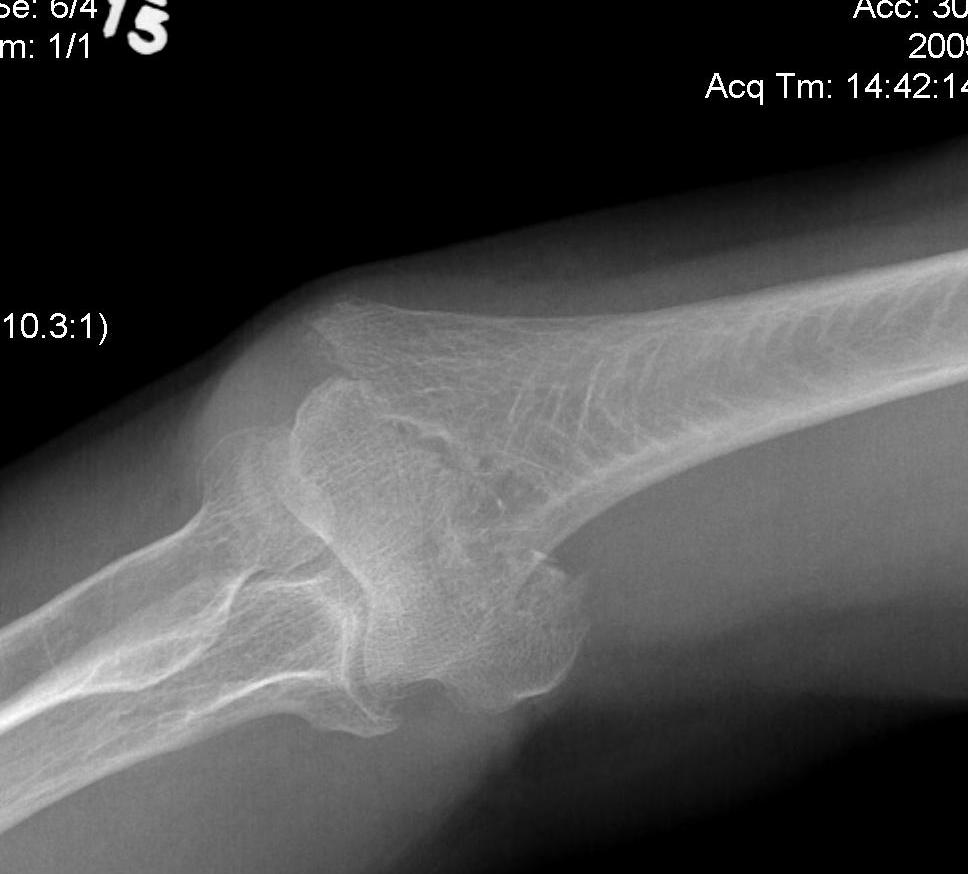

Olecranon Osteotomy

Indication

Complex intra-articular fractures

Technique

AO foundation surgery reference Chevron osteotomy

Chevron

- distally based V shaped

- through bare area of olecranon / smallest width of greater sigmoid notch

- 3 cm from tip